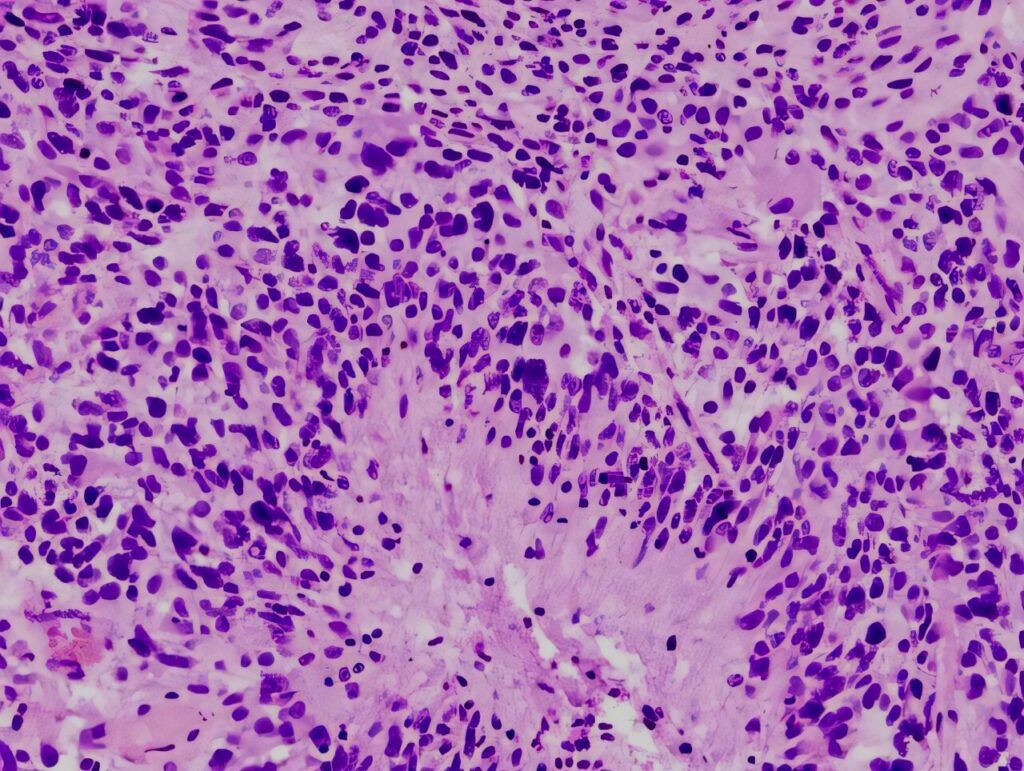

• Biopsy, histology, immunological & genetic tests

In neuro-oncology, understanding the biology of a brain or spinal tumor is essential for selecting the most effective and individualized treatment plan. Diagnostic tools such as biopsy, histology, immunohistochemistry, and molecular testing are required to accurately classify...

Read article